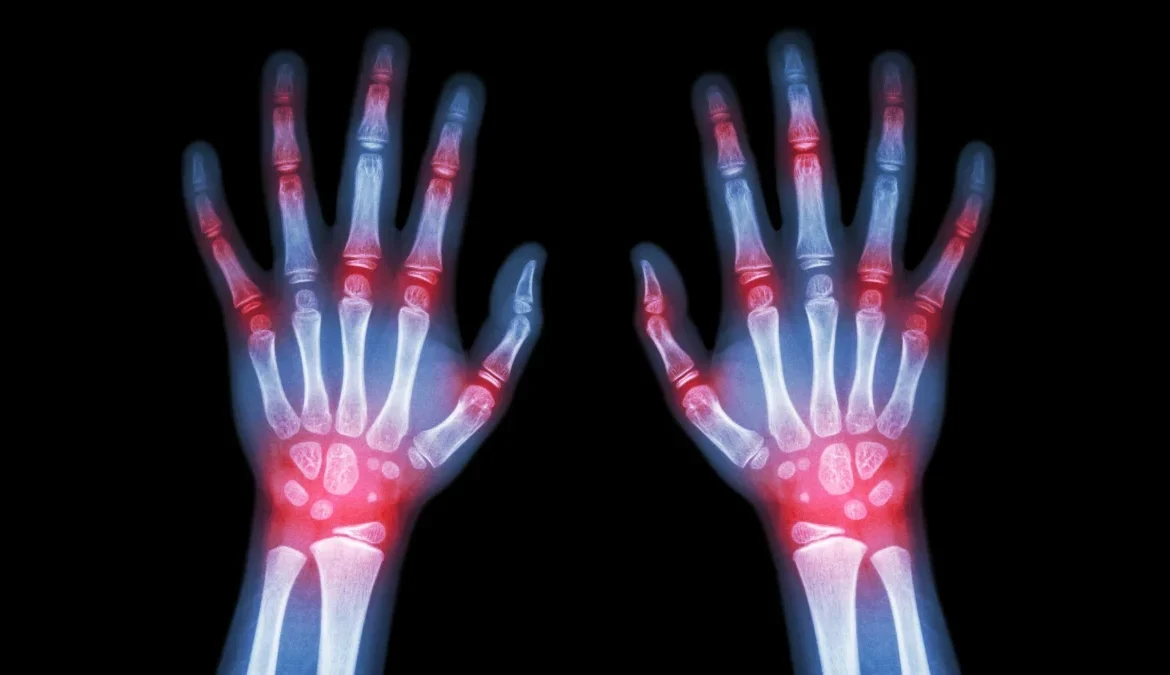

Η ρευματοειδής αρθρίτιδα είναι μια χρόνια πάθηση που προκαλεί φλεγμονή στο σώμα και πόνο στις αρθρώσεις.